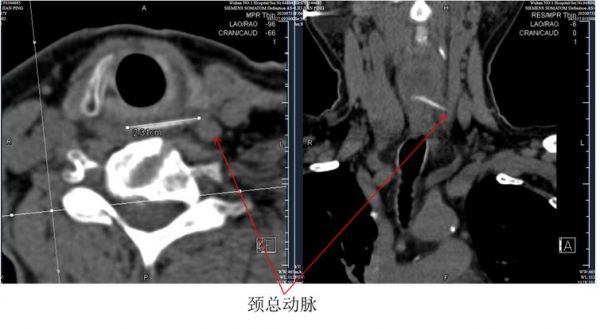

食道CT显示,鱼刺尖端紧邻左侧颈总动脉。

CT结果显示:在第六颈椎处有一条长度为2.31厘米的横形条状致密影,异物左侧尖端戳破食道壁直抵颈总动脉。尖锐的鱼刺一旦扎破动脉,将会引发致死性大出血。当即将刘女士收治入院,紧急安排手术。